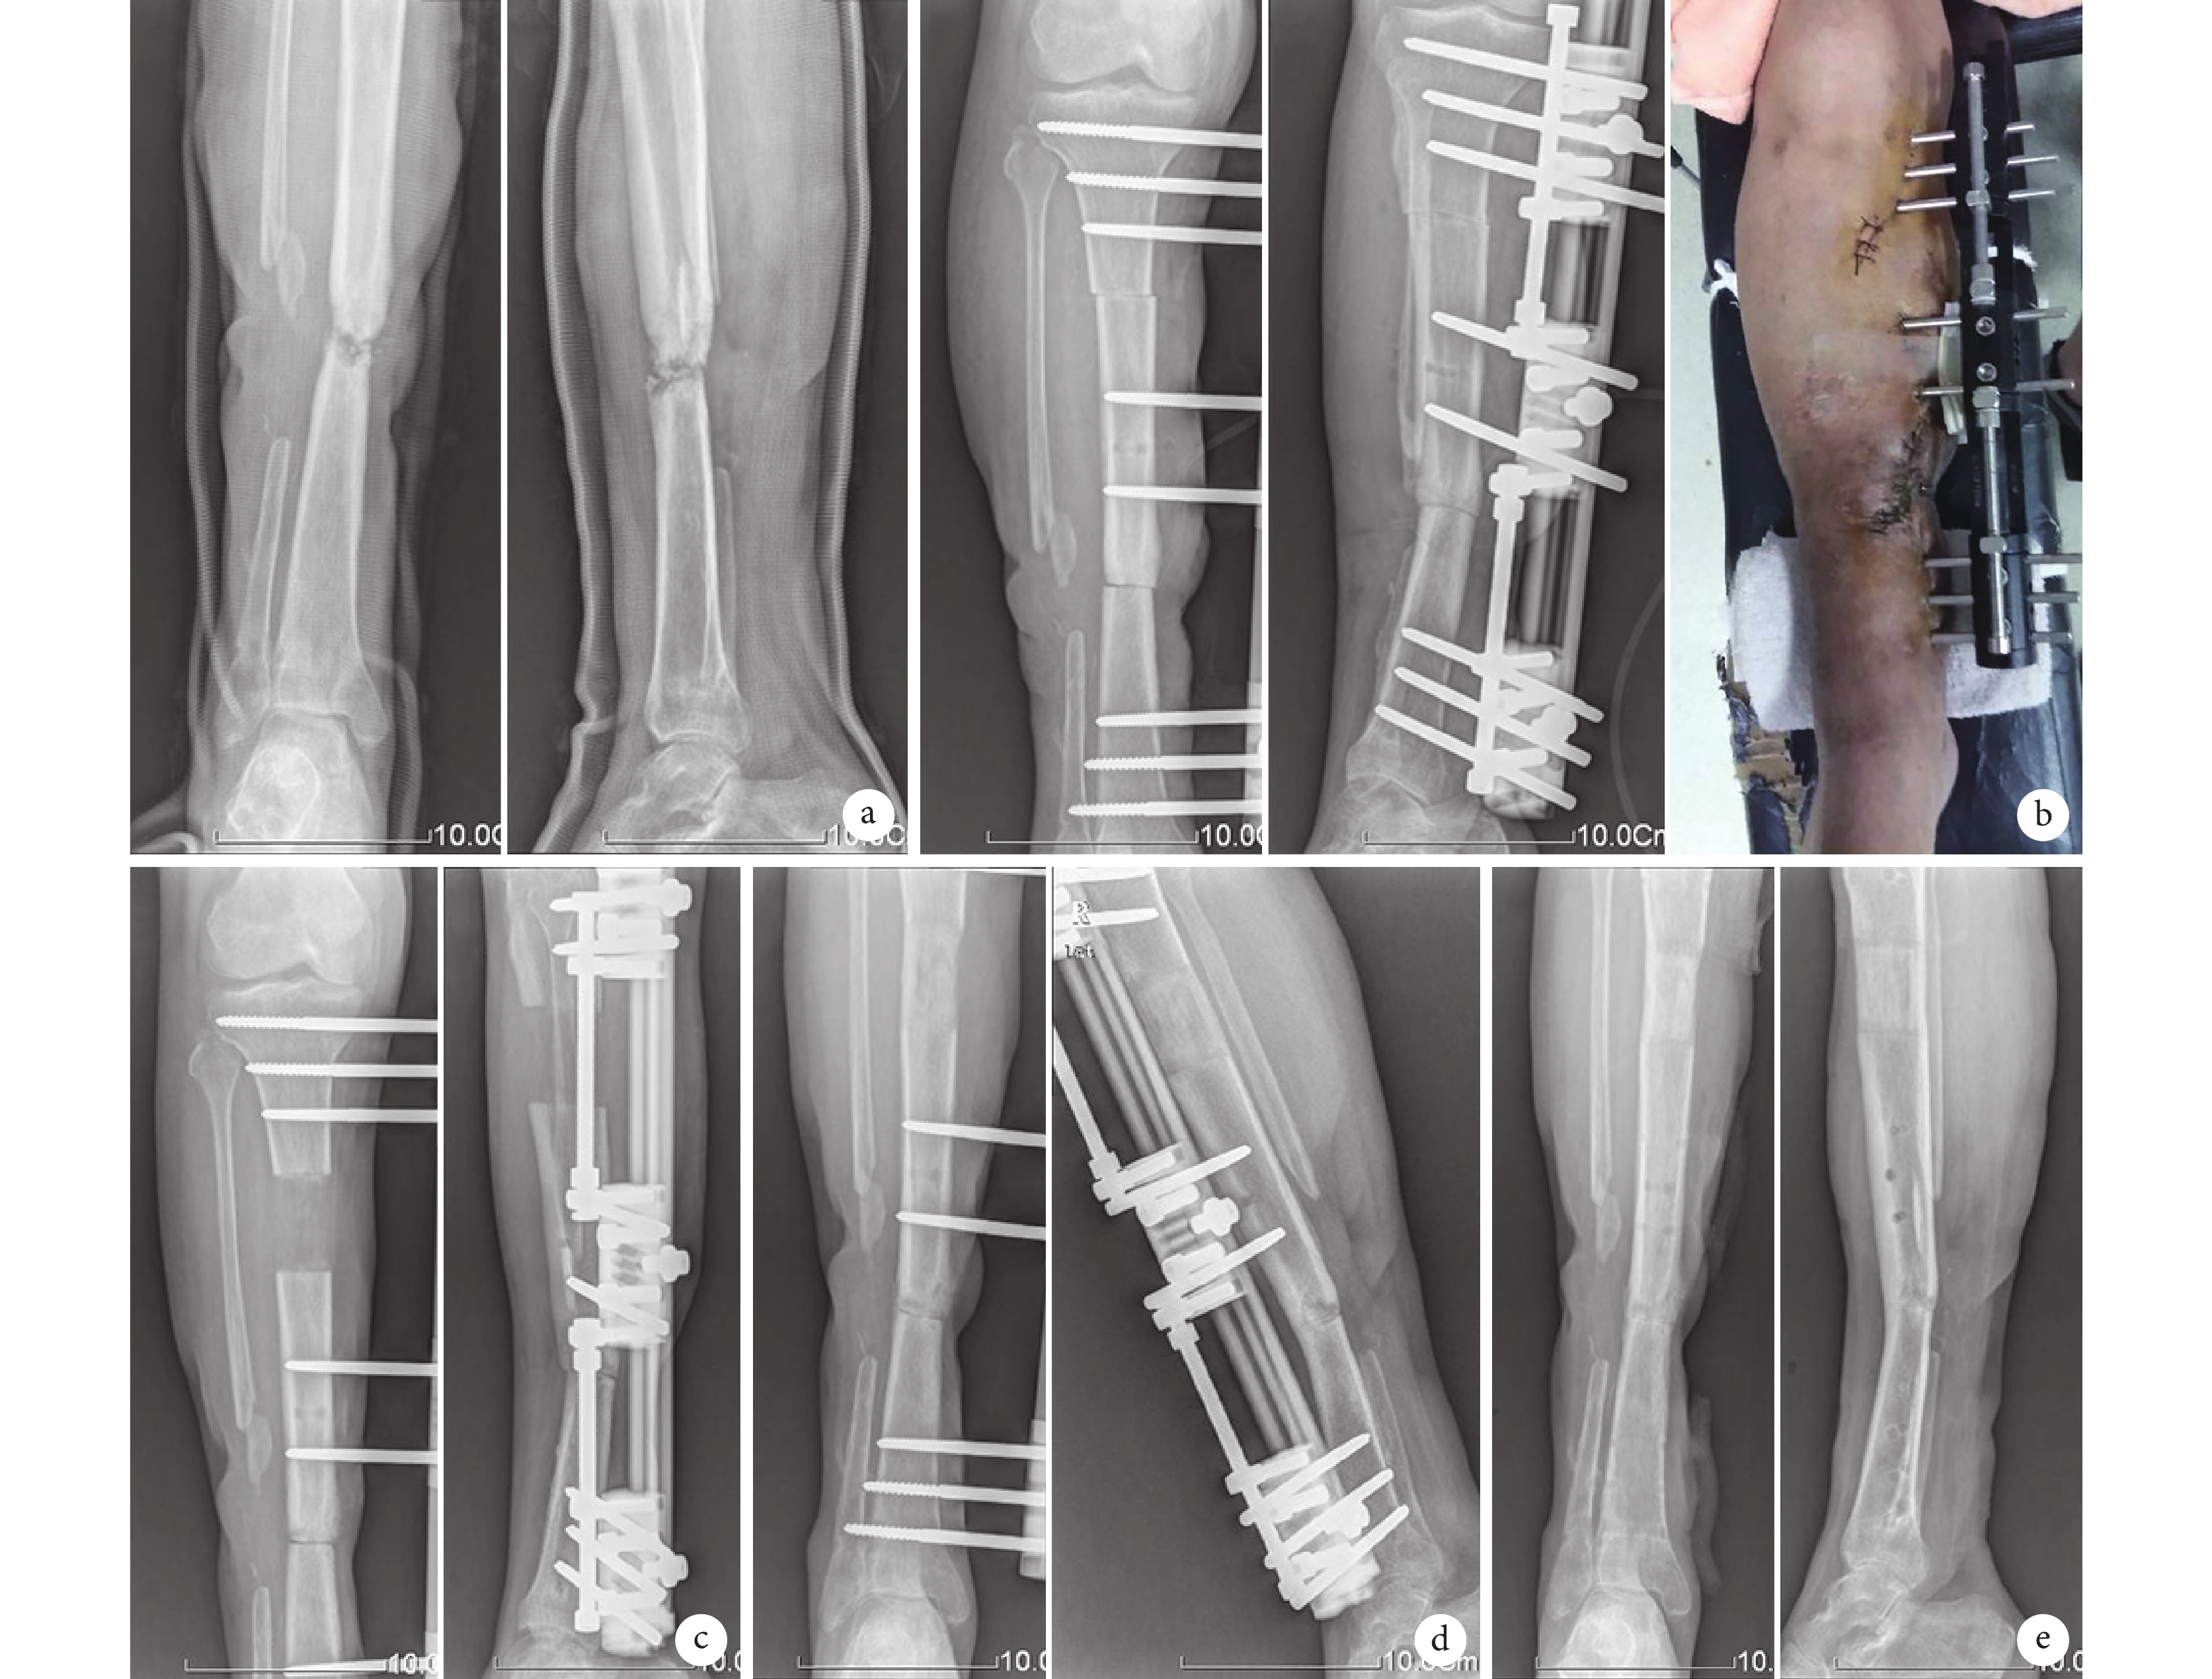

患者 男,48 歲。4 年前因交通事故傷致右脛腓骨開放性骨折并感染,于外院接受 4 次手術治療;因再次摔傷后右小腿再次骨折并傷口流膿入院。診斷:右脛骨慢性骨髓炎并病理性骨折,右脛腓骨開放性骨折術后。入院后取創面組織細菌培養提示為大腸埃希菌感染,行右小腿徹底擴創、切除脛骨病灶骨段 3.5 cm,骨端直接完全對合單臂外固定架加壓固定,近端截骨,腓腸神經營養血管皮瓣完全閉合創面;術后 1 周以 1 mm/d 速度行肢體延長;X 線片示雙下肢等長后,扶拐部分負重行走。術后對合骨端創面順利愈合;X 線片復查,術后 10 個月對合端骨痂及牽張骨痂均達骨性愈合,骨延長時間 2 個月,延長指數 2.15 cm/月,共延長4.3 cm;骨愈合時間 10 個月;根據 Johner-Wruhs 評分評定療效為優。見圖 1。

a. 術前正側位 X 線片示脛骨中段慢性骨髓炎并病理性骨折;b. 病灶骨節段切除短縮術后正側位 X 線片及患肢外觀;c. 術后肢體延長 2 個月正側位 X 線片;d. 術后 6 個月正側位 X 線片示對合骨端骨痂及牽張骨痂生長;e. 術后 10 個月去除外固定后正側位 X 線片示延長端及對合端均達骨性愈合

Figure1. A typical casea. Anteroposterior and lateral X-ray films before operation, showing chronic osteomyelitis of tibia and pathological fracture; b. Anteroposterior and lateral X-ray films and appearance after excision of lesion bone and shortening; c. Anteroposterior and lateral X-ray films after limb lengthening for 2 months; d. Anteroposterior and lateral X-ray films at 6 months after operation, showing callus growth in the opposite end of bone; e. Anteroposterior and lateral X-ray films after removal of external fixator at 10 months after operation, showing bone healing of extended end and opposite end of bone